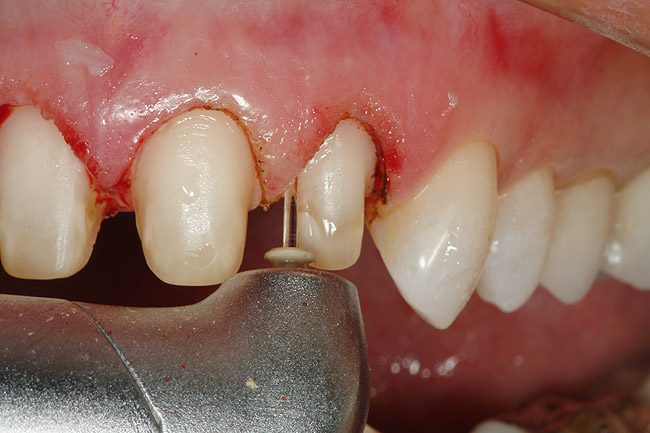

Figure 15  After removal of the defective restoration, it can be seen clinically that the margin of the preparation on the distal of tooth No. 21 was extremely subgingival. The surrounding periodontium was inflamed and hemorrhagic. The laser was used to perform apical repositioning of the bony crest using a closed-flap technique.

Figure 15